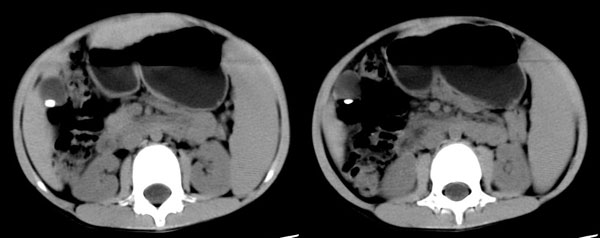

右股动脉穿刺,将导管置入脾动脉远端,造影显示脾明显增大,脾静脉、门静脉未见异常,采用明胶海绵颗粒行脾动脉部分栓塞。

栓塞后造影可见部分脾动脉分支消失,栓塞面积大于50%。

随访:患者术前白细胞2000,血小板7万/l,术后3周复查,白细胞升至9000,血小板升至17万/l,治疗效果满意。